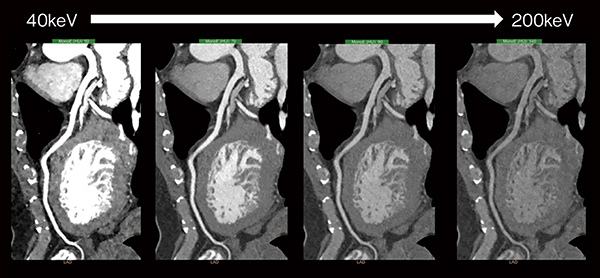

IQonの画像再構成技術の中で最も重要な点は,“anti-correlated noise”の除去である。一般的なDECTの仮想単色X線画像は,X線管球が持つX線スペクトラムの平均エネルギーで最も画像ノイズが少なく,その平均エネルギーから低い,あるいは高いエネルギー領域ではノイズが大きく増加する傾向を認める。このノイズは,光電効果画像とコンプトン散乱画像を結合した際に生じるもので,スペクトラルイメージにおける画質・物質弁別の精度を低下させる一因となる1)。しかし,IQonの画像再構成法では,あらかじめこのanti-correlated noiseを除去することで,仮想単色X線画像の各エネルギー領域において,ノイズの低減された精度の高い画像が得られる(図2)。

図2 仮想単色X線の各エネルギー領域画像

IQonにおける仮想単色X線(以下,MonoE)を用いた画像は,エネルギーを40keVから200keVまで連続的に可変して表示することができる。また,上記のanti-correlated noiseを除去することで,低いエネルギーのMonoE画像(以下,MonoE低keV画像)において,造影剤投与量を低減しても高画質で観察が可能となる。図3の腎機能低下症例では,造影剤を大幅に低減し,MonoE低keV画像を使用することで,低侵襲で診断能の高い検査が可能となっている。また,物質弁別を用いたヨード密度強調画像(以下,Iodine no water)では,ヨード造影剤のコントラストを強調することにより造影効果を有する箇所はさらに視認性が増し,従来のSECTでは診断困難なステント内再狭窄症例における低吸収プラークの視認性向上が期待できる(図4)。